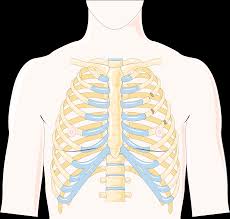

갈비뼈 금간 상태는 외부 충격이나 반복적인 압박으로 인해 뼈에 미세한 균열이 생긴 것을 말합니다. 단순 타박상과 달리 통증이 심하고 숨을 쉴 때, 기침을 할 때 더 크게 아파 일상생활에 불편을 줍니다. 방치할 경우 골절로 진행되거나 폐 손상 같은 합병증으로 이어질 수 있어 주의가 필요합니다.

따라서 증상 인지부터 정확한 진단과 치료까지 체계적인 관리가 필수입니다. 이번 글에서는 갈비뼈 금간 증상, 진단 방법, 치료법을 자세히 정리했습니다. 아래 요약표로 쉽게 확인해보세요!